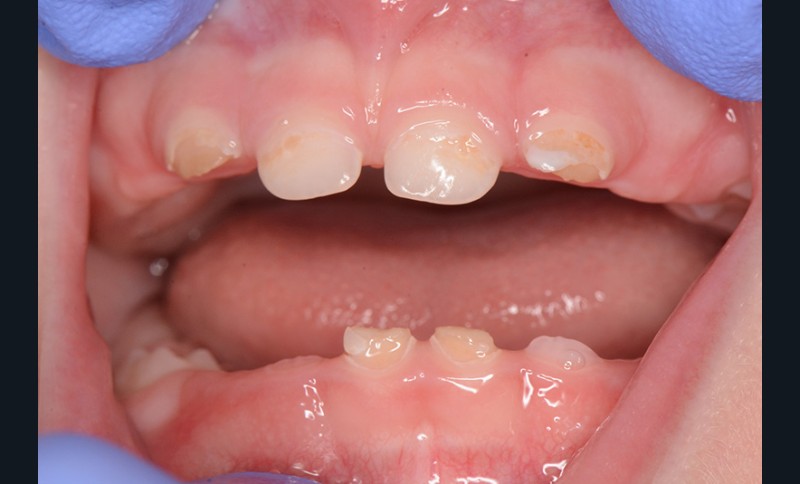

En France, la carie de la petite enfance (CPE) est souvent négligée chez l’enfant en denture temporaire, 24 % des dents temporaires affectées par des lésions carieuses cavitaires n’étant pas traitées, alors que la prévalence mondiale atteint 8,8 % [1]. Les enfants affectés ne sont souvent amenés en consultation que dans les cas sévères (tableau 1) lorsque les lésions nécessitent des réhabilitations prothétiques à envisager après correction du risque carieux (fig. 1).